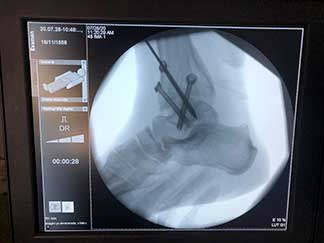

Artículo de trabajo con equipo de Primera División “Tuzos de Pachuca”

Durante mi entrenamiento en mi segundo fellow en cirugía articular y lesiones deportivas, tuve la oportunidad de hacer una rotación en el hospital CEMA by FIFA (Centro de Excelencia Médica en Altura) en Pachuca Hidalgo, donde brindé atención médica y quirúrgica en las instalaciones de la Universidad a pacientes deportistas profesionales y de alto rendimiento, miembros del equipo de fútbol “Tuzos de Pachuca”.